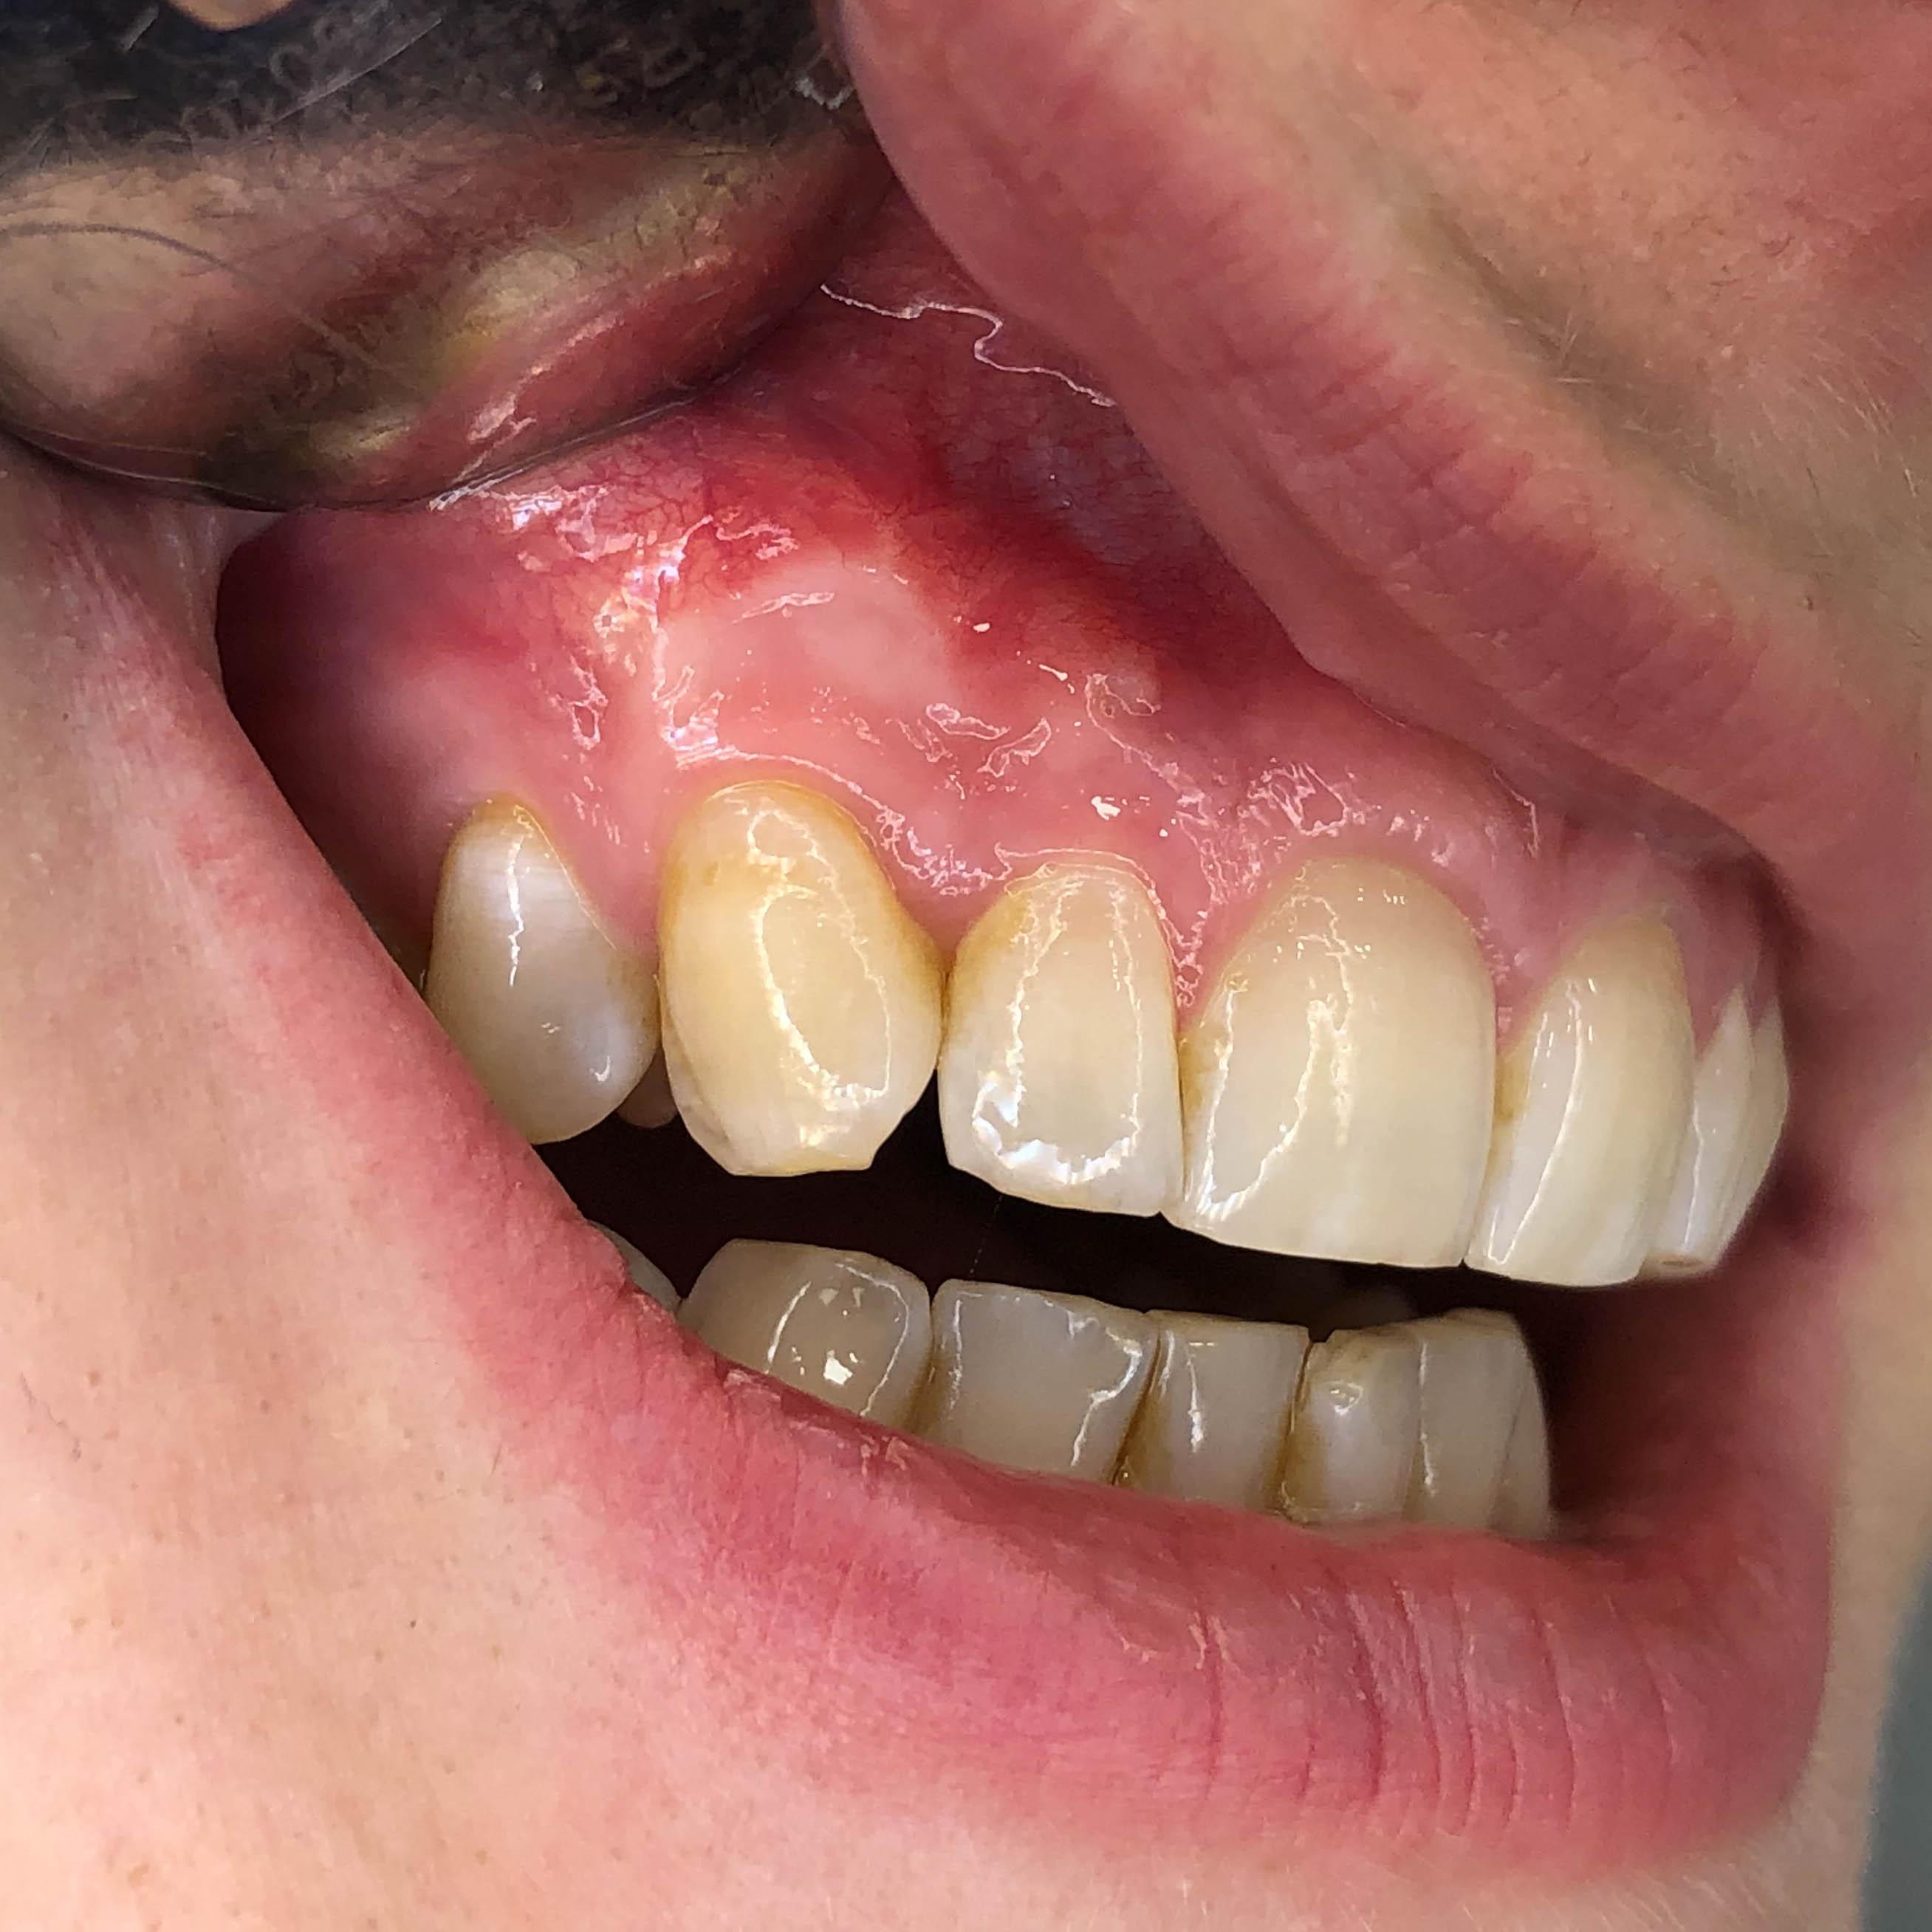

Papillóma eltávolítás

A kimetszett elváltozást szövettani vizsgálatra küldtük, ami igazolta az elváltozás jóindulatú voltát.